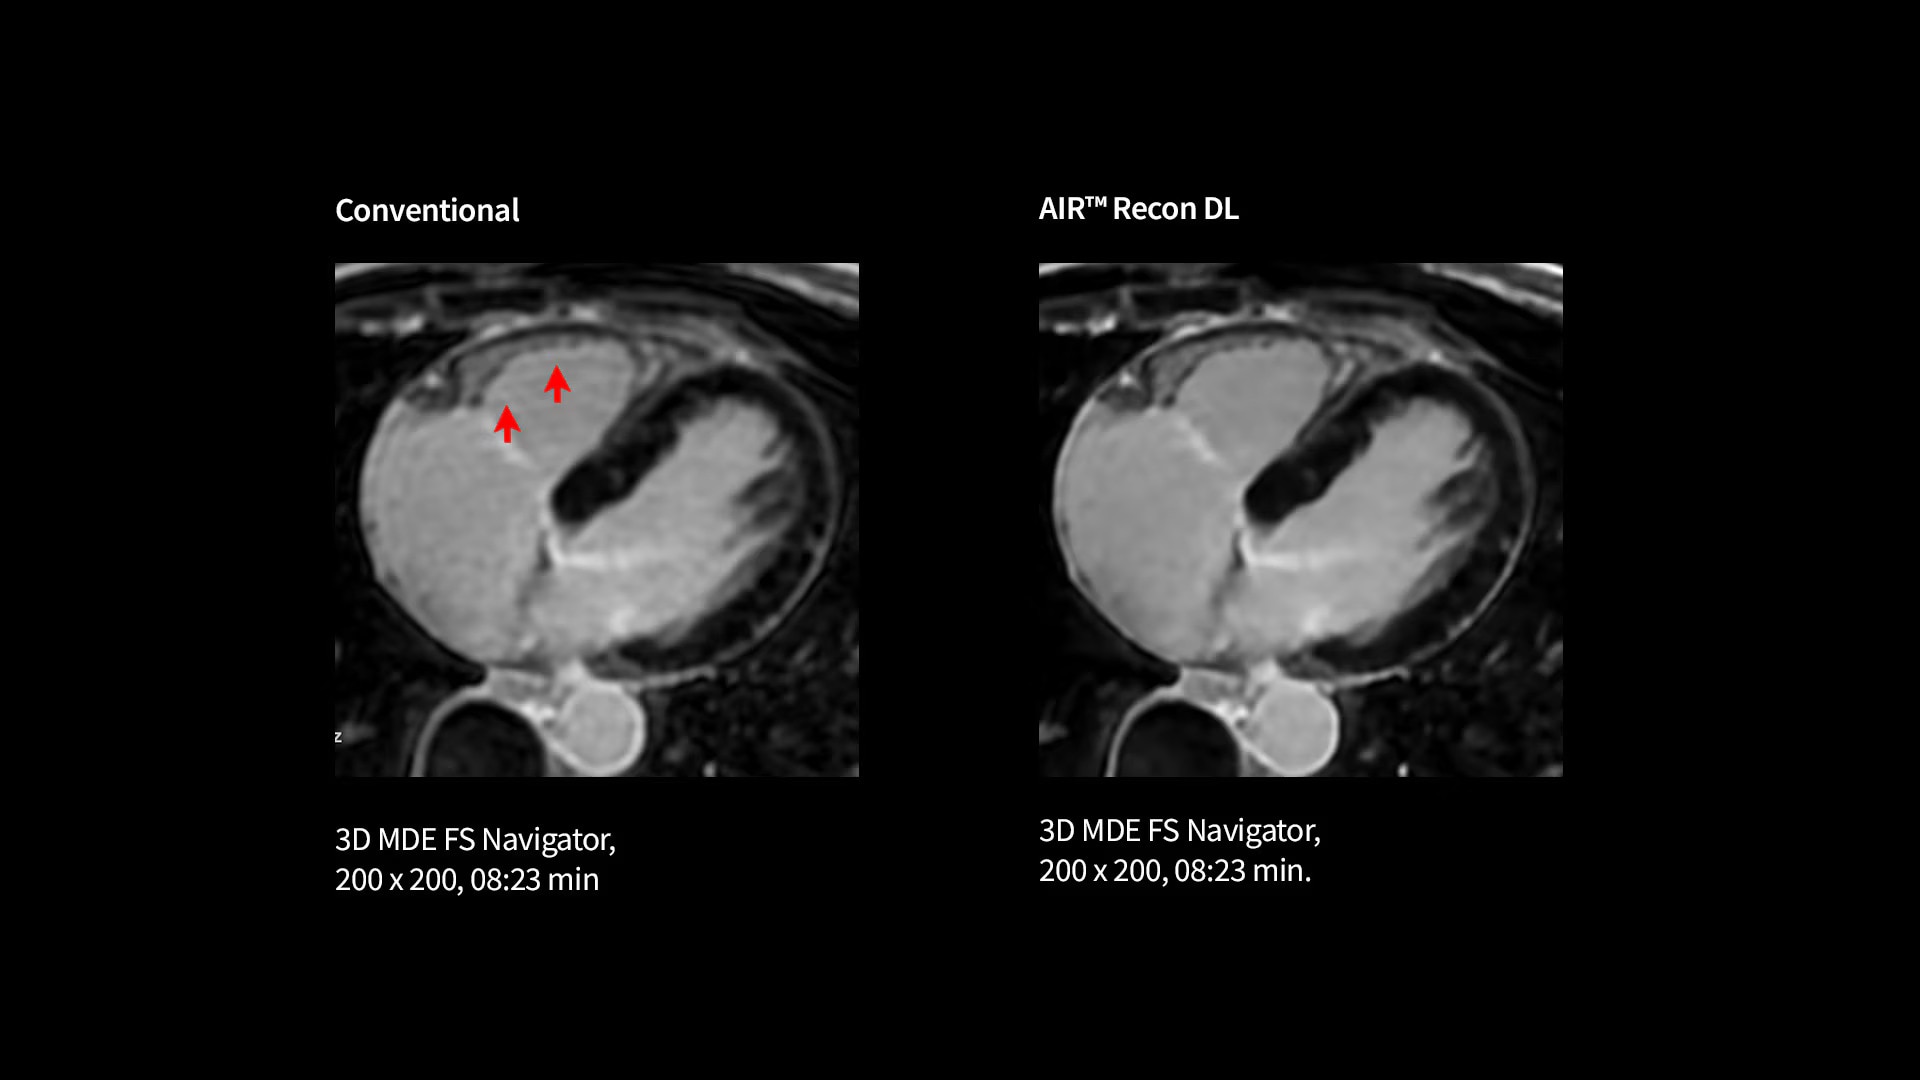

Capture clarity

Improve SNR and image sharpness by up to 60% with AIR™ Recon DL